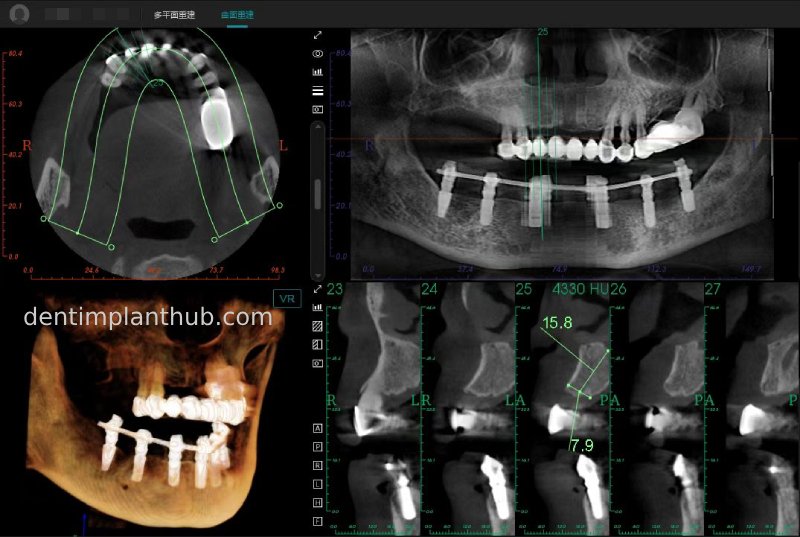

Maxillary condition as shown by CBCT on 13/5/24

16

14

12

22

24

26

Details of implant sites, protocols, implant types, composite abutments, 13.5.24

16, implant model 4810, requires an internal elevation of the maxillary sinus floor and an RC series straight composite abutment;

14, implant model 4812, requires an RC series 15° composite abutment;

12, implant model 4112, requires an RC series 30° composite abutment;

22, implant model 4112, requires an RC series 30° composite abutment;

24, implant model 4812, requiring an RC Series 15° composite abutment;

26, implant model 4810, requiring an internal maxillary sinus floor lift, requiring an RC Series straight composite abutment;